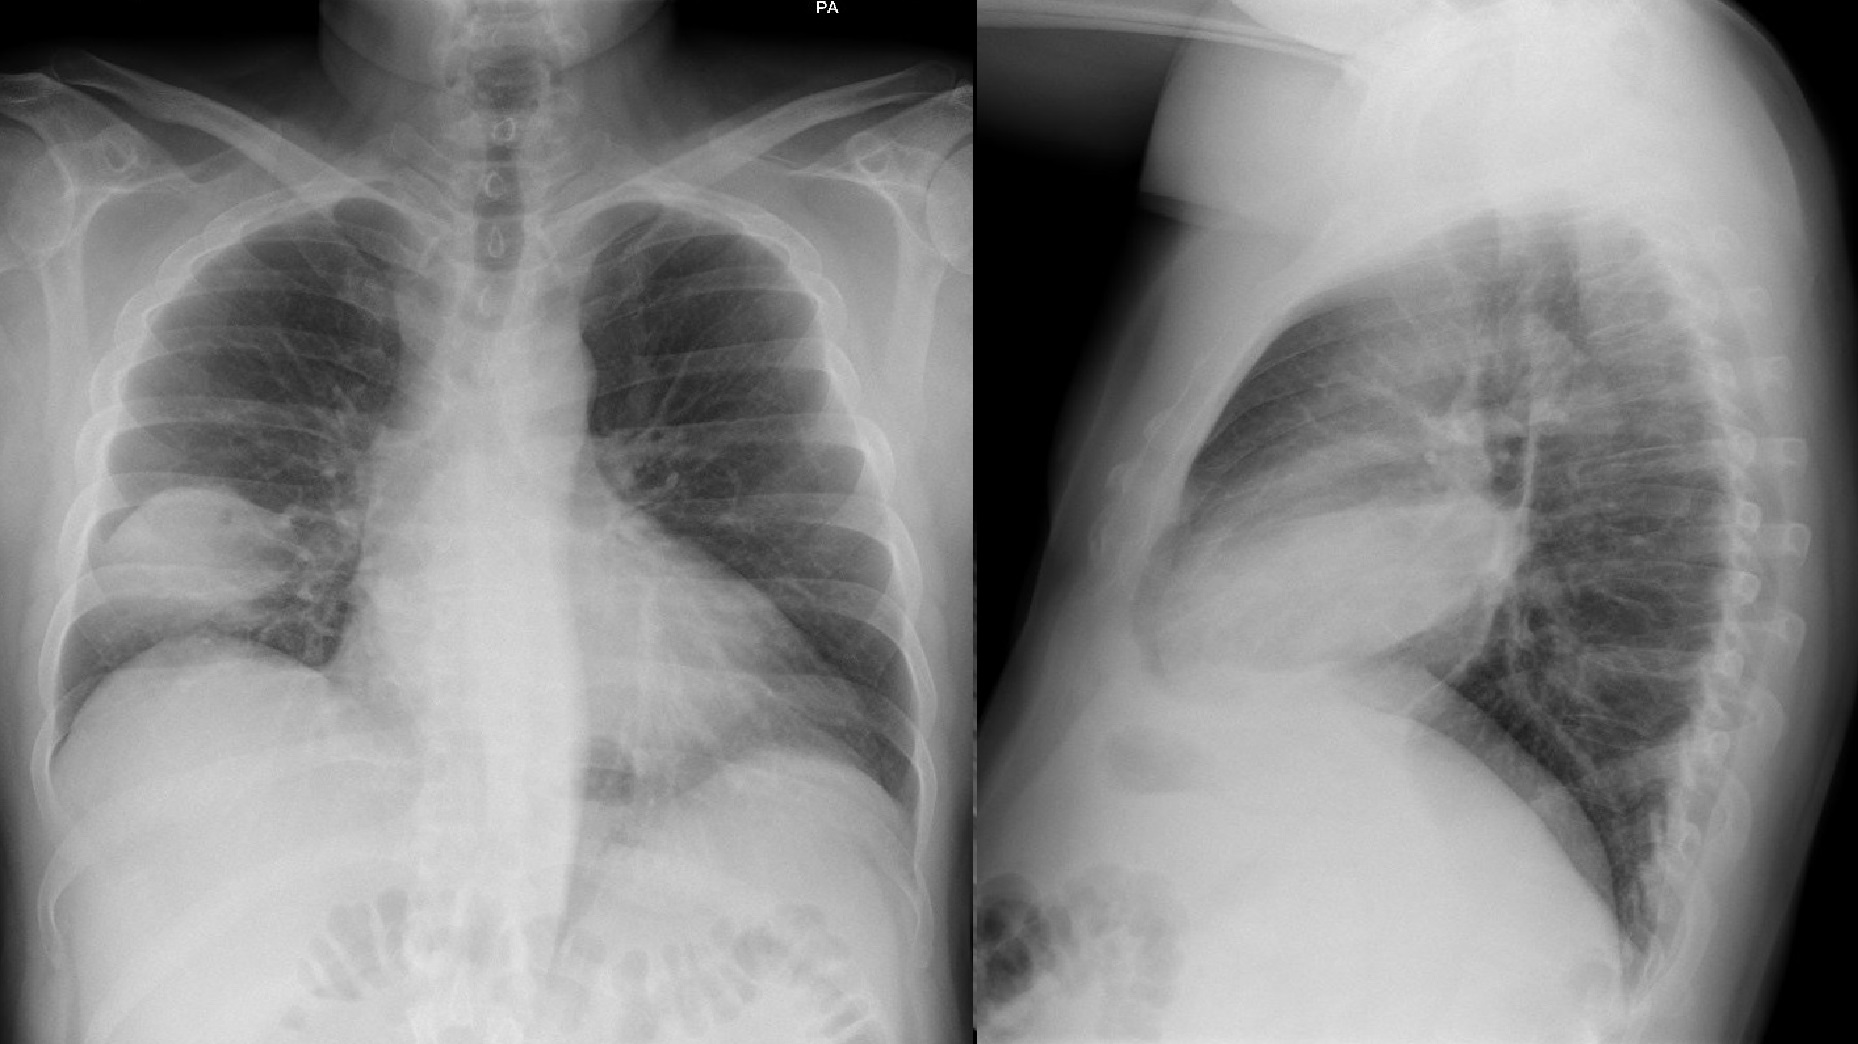

Otras pruebas complementarias realizadas (si existen)

Se trata de dos casos en los que los hallazgos clínicos y las pruebas complementarias convencionales no hubieran llevado al diagnóstico ni tratamiento adecuados. En el primer caso por una radiografía normal y en el segundo por sintomatología no sospechosa que podría no haber indicado dicha radiografía. La disponibilidad de ecógrafo en la consulta facilita su utilización de inmediato tras la auscultación, detectando las lesiones y consiguiendo una mayor precisión diagnóstica y terapéutica.